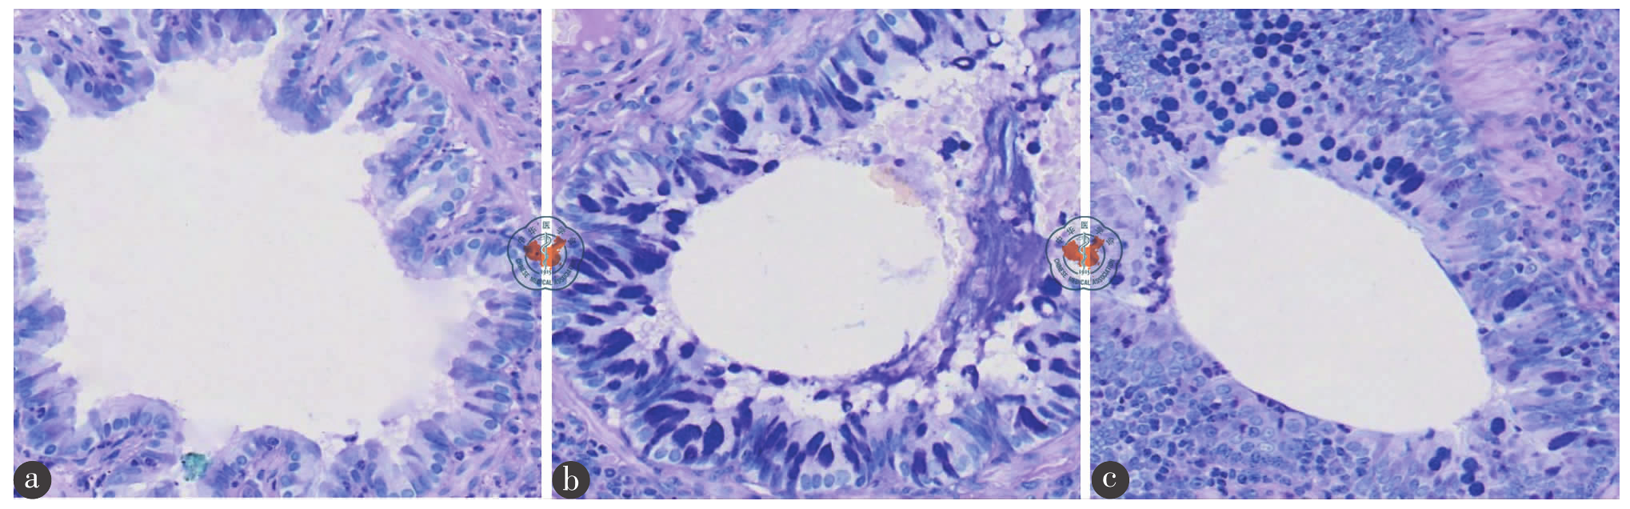

各组大鼠肺组织W/D,BALF中TNF-α、PCⅢ的含量,肺组织NF-κBp65及TLR4蛋白表达的比较,差异均有统计学意义(F = 136.155、139.639、95.353、94.034、67.540,P均< 0.001)。且与对照组比较,ARDS组和姜黄素组肺组织W/D[(3.99 ± 0.16)、(5.53 ± 0.15)、(4.81 ± 0.24)],BALF中的TNF-α[(61 ± 5)、(219 ± 25)、(157 ± 21)ng/L]和PCⅢ[(0.67 ± 0.22)、(61.66 ± 11.95)、(35.62 ± 9.64)μg/L]含量,肺组织中NF-κBp65及TLR4蛋白表达水平均显著升高,且ARDS组更高(P均< 0.05)。Masson染色显示,ARDS组肺间质呈广泛胶原纤维沉积,姜黄素组肺间质呈轻度弥漫性胶原纤维沉积。AB-PAS染色可见,ARDS组支气管上皮杯状细胞化生、姜黄素组支气管上皮杯状细胞轻度化生。

The W/D, TNF-α, PCⅢ, TLR4 protein and NF-κBp65 protein among the three group all showed significant differences (F = 136.155, 139.639, 95.353, 94.034, 67.540; all P<0.001). Compared with the control group, the W/D [(3.99 ± 0.16), (5.53 ± 0.15), (4.81 ± 0.24)], TNF-α [(61 ± 5), (219 ± 25), (157 ± 21) ng/L], PCⅢ [(0.67 ± 0.22), (61.66 ± 11.95), (35.62 ± 9.64) μg/L], TLR4 protein and NF-κBp65 protein increased obviously in the ARDS and curcumin groups, and they increased most in the ARDS group (all P < 0.05). Masson staining showed extensive collagen deposition in the ARDS group and mild diffuse collagen deposition in the curcumin group. AB-PAS staining showed goblet cell metaplasia in the ARDS group and mild goblet cell metaplasia in the curcumin group.

图3 各组大鼠肺组织支气管病理变化